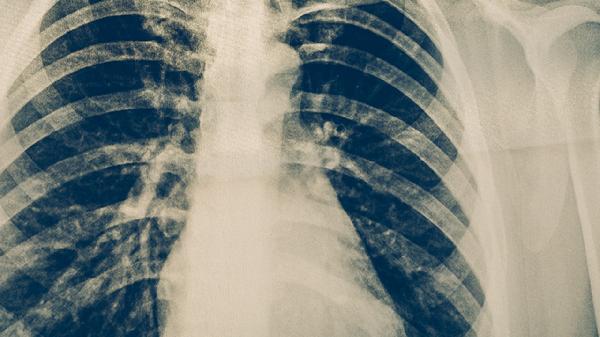

肺心病主要表現(xiàn)為呼吸困難、心悸、下肢水腫、乏力、咳嗽咳痰等癥狀。肺心病通常由慢性阻塞性肺疾病、肺動(dòng)脈高壓、肺栓塞等因素引起,可能伴隨發(fā)紺、頸靜脈怒張、肝大等體征。

呼吸困難是肺心病最常見的癥狀,早期表現(xiàn)為活動(dòng)后氣促,隨著病情進(jìn)展可出現(xiàn)靜息狀態(tài)下呼吸困難。呼吸困難可能與肺動(dòng)脈高壓導(dǎo)致右心負(fù)荷加重有關(guān),患者常伴有呼吸頻率增快、口唇發(fā)紺等癥狀。急性加重期可遵醫(yī)囑使用沙丁胺醇?xì)忪F劑、氨茶堿片、呋塞米片等藥物緩解癥狀。